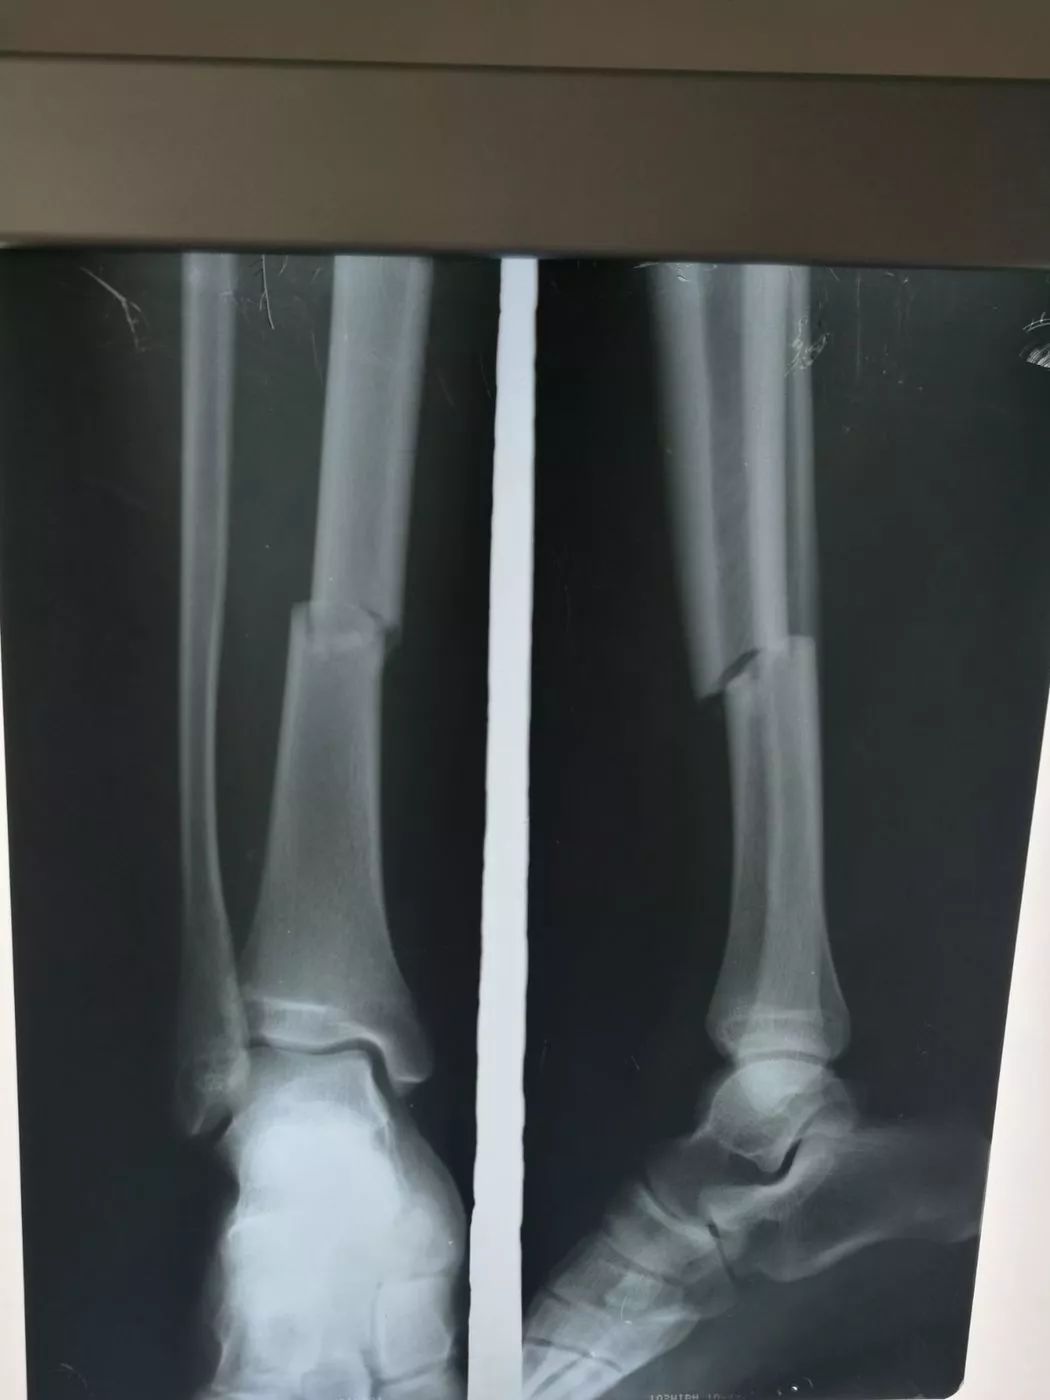

受傷した 画像所見より左腓骨遠位端骨折と診断された前 脛腓靭帯付着部の剥離骨折, 腓骨のらせん骨折および脛骨後 果の骨折からLaugeHansen分類ではSER型stageⅢであった 受傷後9日目にロッキングプレートを用いた骨接合術が施行 された左足首の骨折。 過去に足首を捻挫または骨折をして、治ってからも予防のためにサポーターを着用していませんか? サポーターを着用していると捻挫の予防になるかもしれません。しかし、時に逆効果になってしまう場合もあります。 &n交通事故の被害に遭い、脛骨骨折や腓骨骨折の怪我を。 その後、もしも後遺症が残ってしまったとしたら。 これからも長く続く治療やリハビリの生活では、 脛骨骨折・腓骨骨折から回復するために支払う治療費 怪我をしたことや後遺症が残ったことによる精神的苦痛に対する慰謝料 将来

胫腓骨骨折术前 胫腓骨骨折术后 胫腓骨折术前 胫腓骨骨折 Www Dingjisc Com

一例严重的胫腓骨远端粉碎骨折